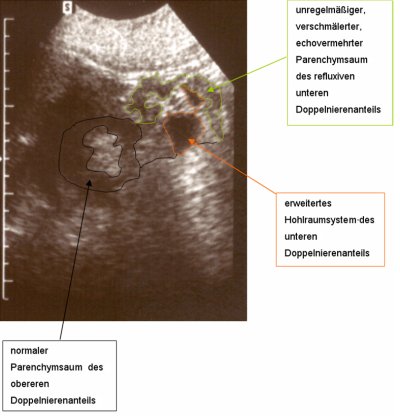

Bei dem Jugendlichen fand sich eine Doppelniere links mit hydronephrotischen Doppelnierenanteil bei VUR III.° in den unteren Anteil. Es bestand ein rezidivierender fieberhafter Harnwegsinfekt. Die Sonographie ergab eine unauffällige rechte Niere, links eine Doppelniere mit regelrechtem oberen und einem hydronephrotischen unteren Nierenanteil (Abbildung 7). Die Harnblase war unauffällig. Im Ausscheidungsurogramm fand sich eine Doppelniere links mit dilatiertem unteren Nierenanteil bei Ureter duplex (Abbildung 8a). Der Kontrastmittelabstrom aus dem unteren Nierenanteil war verzögert (Abbildung 8b). Im Zystogramm fand sich ein Vesikoureteraler Reflux (III.°) in das untere Nierenhohlraumsystem. In der Zystoskopie zeigte sich ein Golflochostium des fehleinmündenden unteren Harnleiters links. Die Nierensequenzszintigraphie ergab in der Gesamtclearence 288 ml/min (NB: > 255 ml/min) (Abbildung 8c).